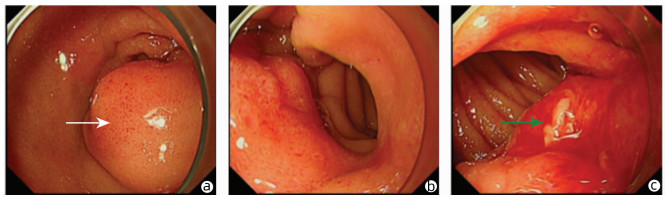

Successful treatment of Bouveret ' s syndrome due to giant duodenal gallbladder stones through the anterior wall of the stomach: A case report

2022, 38(3): 636-638. DOI: 10.3969/j.issn.1001-5256.2022.03.028

Abstract(974) HTML (241) PDF (2628KB)(64)

Abstract: